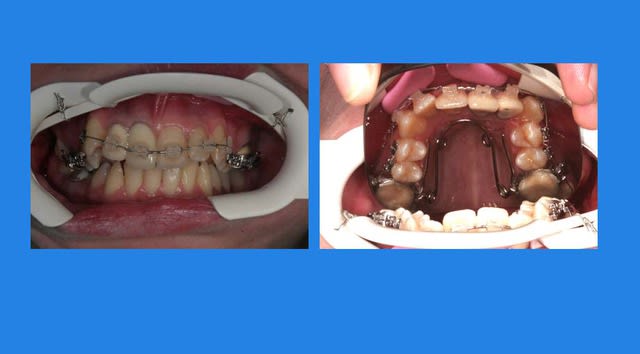

Suite :

J’ai pensé qu’il suffisait de déposer le Q.H. pour que les mouvements parasites s’arrêtent d’eux m

il n’en est rien : photo un mois après

malgré tout, les formes d’arcades s’arrangent !

a suivre Bjc.

6 tcnvtt - Eugenol

7 aokywu - Eugenol

j'avais fabriqué une Cl. II.

là, j'ai eu un moment de découragement

Je suis face à plusieurs Pbs.

continuer mon reformage tout en stoppant la version des Ant.

et la réduire, mais pour cela, il me faudra utiliser des élastiques de Cl. II. avec des arcs rigides et donc avoir fini le reformage

c’est la quadrature du cercle, il me faut choisir

je garde en priorité le reformage et pour bloquer (et essayer de commencer à réduire) la version des Ant. j’utilise un arc à mémoire de forme 16*x16* que je vais faire travailler avec du torque sur les Ant. en ligaturant en inter-actif et en post en passif, en ligaturant passif

l’effet d’expansion se surajoutera aux forces musculaires de l’orbiculaire pour stabiliser les Ant.

résultat: la situation s’améliore, j’ai pu inverser les tendances grâce à l’arc 16*x16* austénitique utilisé en parti en passif, et en parti en inter-actif, c. a. d. en gardant de la glisse tout en mettant du torque

(le 16*x16* est un arc magique que l’on ne peut malheureusement pas bien utiliser avec tous les systèmes à forces faibles)

OUF !!!

@+ Bjc.

8 wlbjpg - Eugenol

Img 0812 mvp6i0 - Eugenol